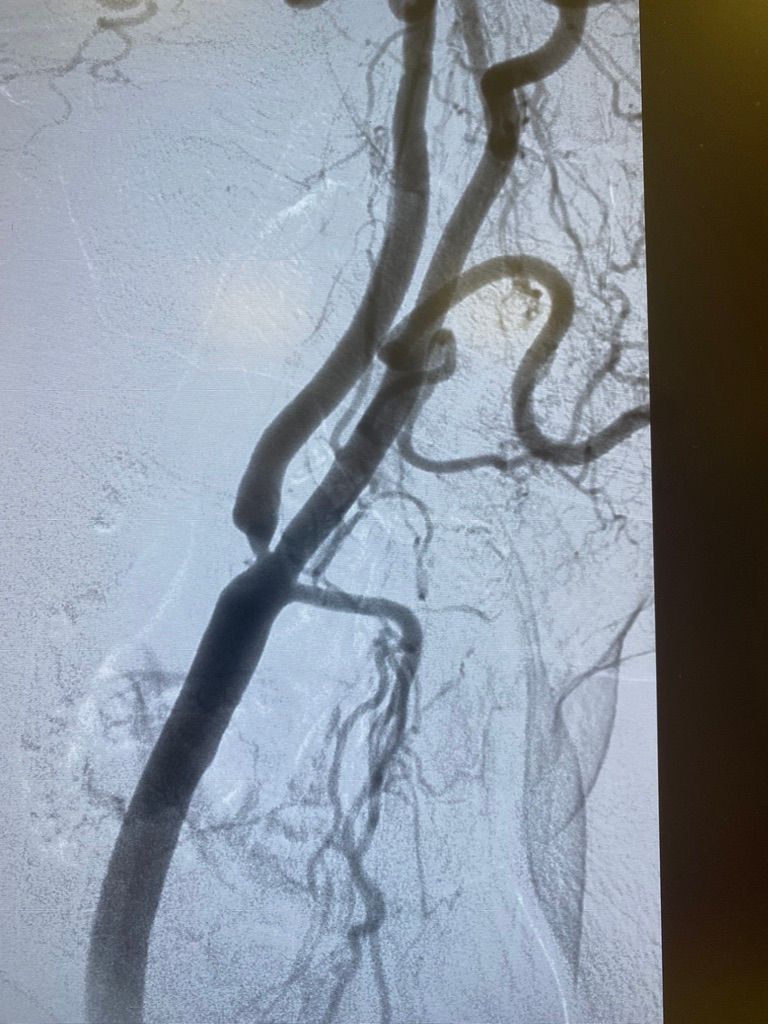

Dal 1997 al 2009 ha lavorato a tempo pieno presso Maria Cecilia Hospital di Cotignola come Cardiologo interventista eseguendo procedure interventistiche di PTCA sul distretto coronarico, carotideo, PTA del distretto iliaco-femorale, renale, e tibiale; Procedure percutanee di impianto di endoprotesi nel in aorta toracica e addominale, impianto percutaneo di valvole aortiche (TAVI), chiusura di Difetti interatriali e forami ovali.

VALUTAZIONE DI PROCEDURE INTERVENTISTICHE (vascolare, patologie delle carotidi, delle arterie iliacofemorali, arterie tibiali nel piede diabetico, aorta addominale e toracica) E CARDIOLOGICHE (angioplastiche coronariche, TAVI, chiusura di difetti interatriali e forami ovali pervi)